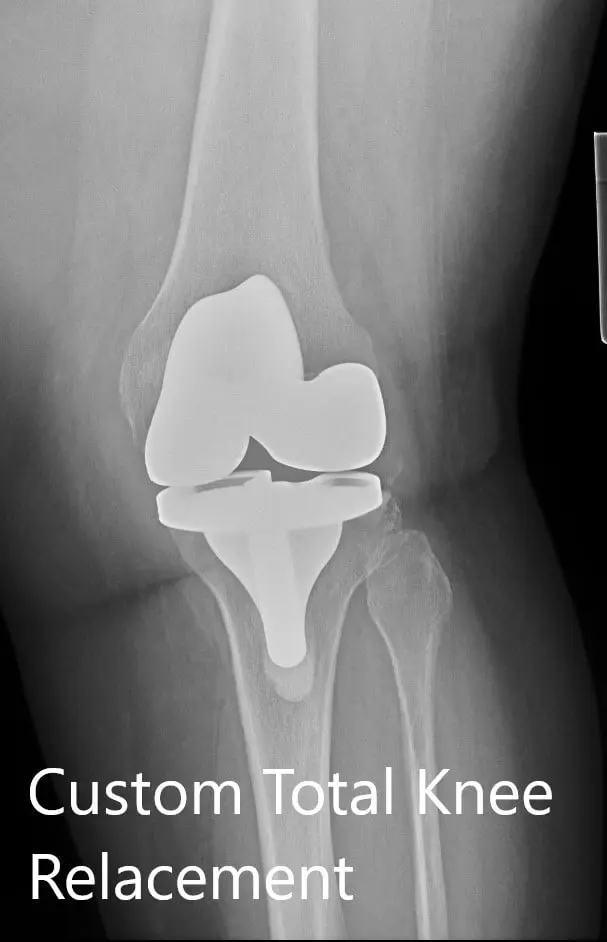

Postoperative X-ray showing the AP and lateral view of the left knee

Recovery was excellent in the post-op period. The vitals were stable and there was no distal neurological deficit. He was able to walk the same day of the procedure. Aspirin 325 mg BID was started for deep vein thrombosis prophylaxis. The pain was managed with medications. Physical therapy was initiated for increasing range of motion and strengthening.

Three months post-op, the patient demonstrated a full range of motion with zero pain. He was able to walk, drive a car and do daily activities without experiencing any pain. He reported decreased pain in the right knee secondary to offloading of the weight. He follows up as needed.